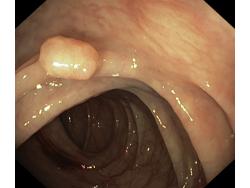

Polipy